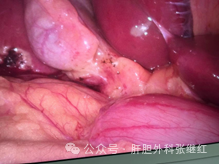

(A:胆总管;B:胆囊管;C:Rouviere沟;D胆囊壶腹)

胆囊、胆囊底、胆囊壶腹部、肝下间隙、胆囊三角、肝门横沟、右肝蒂入肝处、Rouviere沟等均是胆囊切除的重要解剖标志。

胆囊三角、肝总管和胆总管是腹腔镜胆囊切除中最重要的解剖结构。